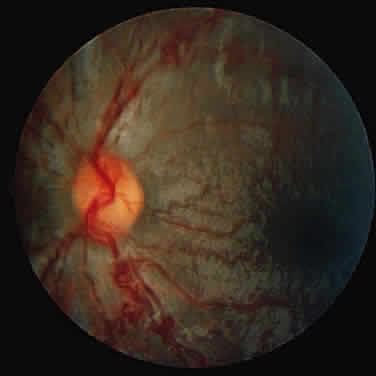

Type B NPD has a variable phenotype, with only visceral involvement. It is diagnosed in childhood between 3 and 11 years of age, or in adult life with hepatosplenomegaly and progressive pulmonary infiltrates that cause the major disease complications.139 Most patients have a normal intellect and survive into adulthood. Patients with type B NPD are of mixed ethnic backgrounds. Harzer and associates140 were first to demonstrate a low sphingomyelinase level in this disease.

A unique retinal abnormality, the macular halo syndrome, has been reported in type B NPD by Cogan and Kuwabara135 and consists of a ring of opacities around the macula that causes no visual impairment (Fig. 15). This abnormality has been reported by several authors.141–143The crystalloid halo which measures about half the disc diameter occurs at the outer edge of the retina mainly in Henle's fiber layer causing only minor obstruction of the overlying vessels. Matthews and associates144 proposed that the macular halo represents the mildest form of a cherry-red spot in the ganglion cell layer of the retina. Their findings are in conflict with those of Cogan et al.138 The precise location of the opacities in the retina remains uncertain because of the lack of histopathology. The available clinical data suggest that such opacities are permanent.

Fig. 15. Macular halo in a patient with Niemann-Pick type B.